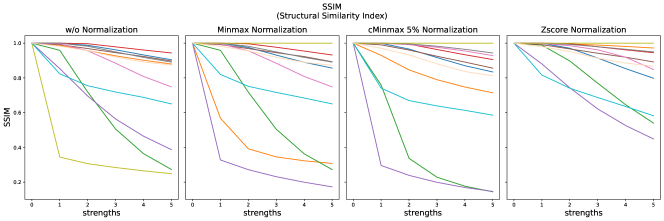

The results for all strengths are given in Figs. A.1-A.4. In Tab. 5 - 8, the results for distortions of maximal strength (s=5) are summarized.

For all applied distortions, all reference metric scores monotonously measure lower similarity for increasing distortion strengths.

SSIM similarity scores for strong blurring are very high, compared to most other distortions.

PSNR scores generally display only very small changes for strengths larger than 2 (see Fig. A.1). PSNR values are higher for Zscore normalization.

Images distorted with Gaussian blurring and ghosting artifacts receive very high PSNR similarity scores, especially with small distortion strengths.

The experiments and adverse examples demonstrate specific strengths and weaknesses of the analyzed metrics. Although SSIM and PSNR are frequently used for the evaluation of synthetic MR images, they are strongly decreased by constant intensity shifts if no normalization is applied. PSNR is very dependent on the kind of normalization, which complicates its use as a comprehensive metric for comparing studies of different authors. SSIM underestimates blurring and thereby favors blurred or additionally blurred images over other distortions.